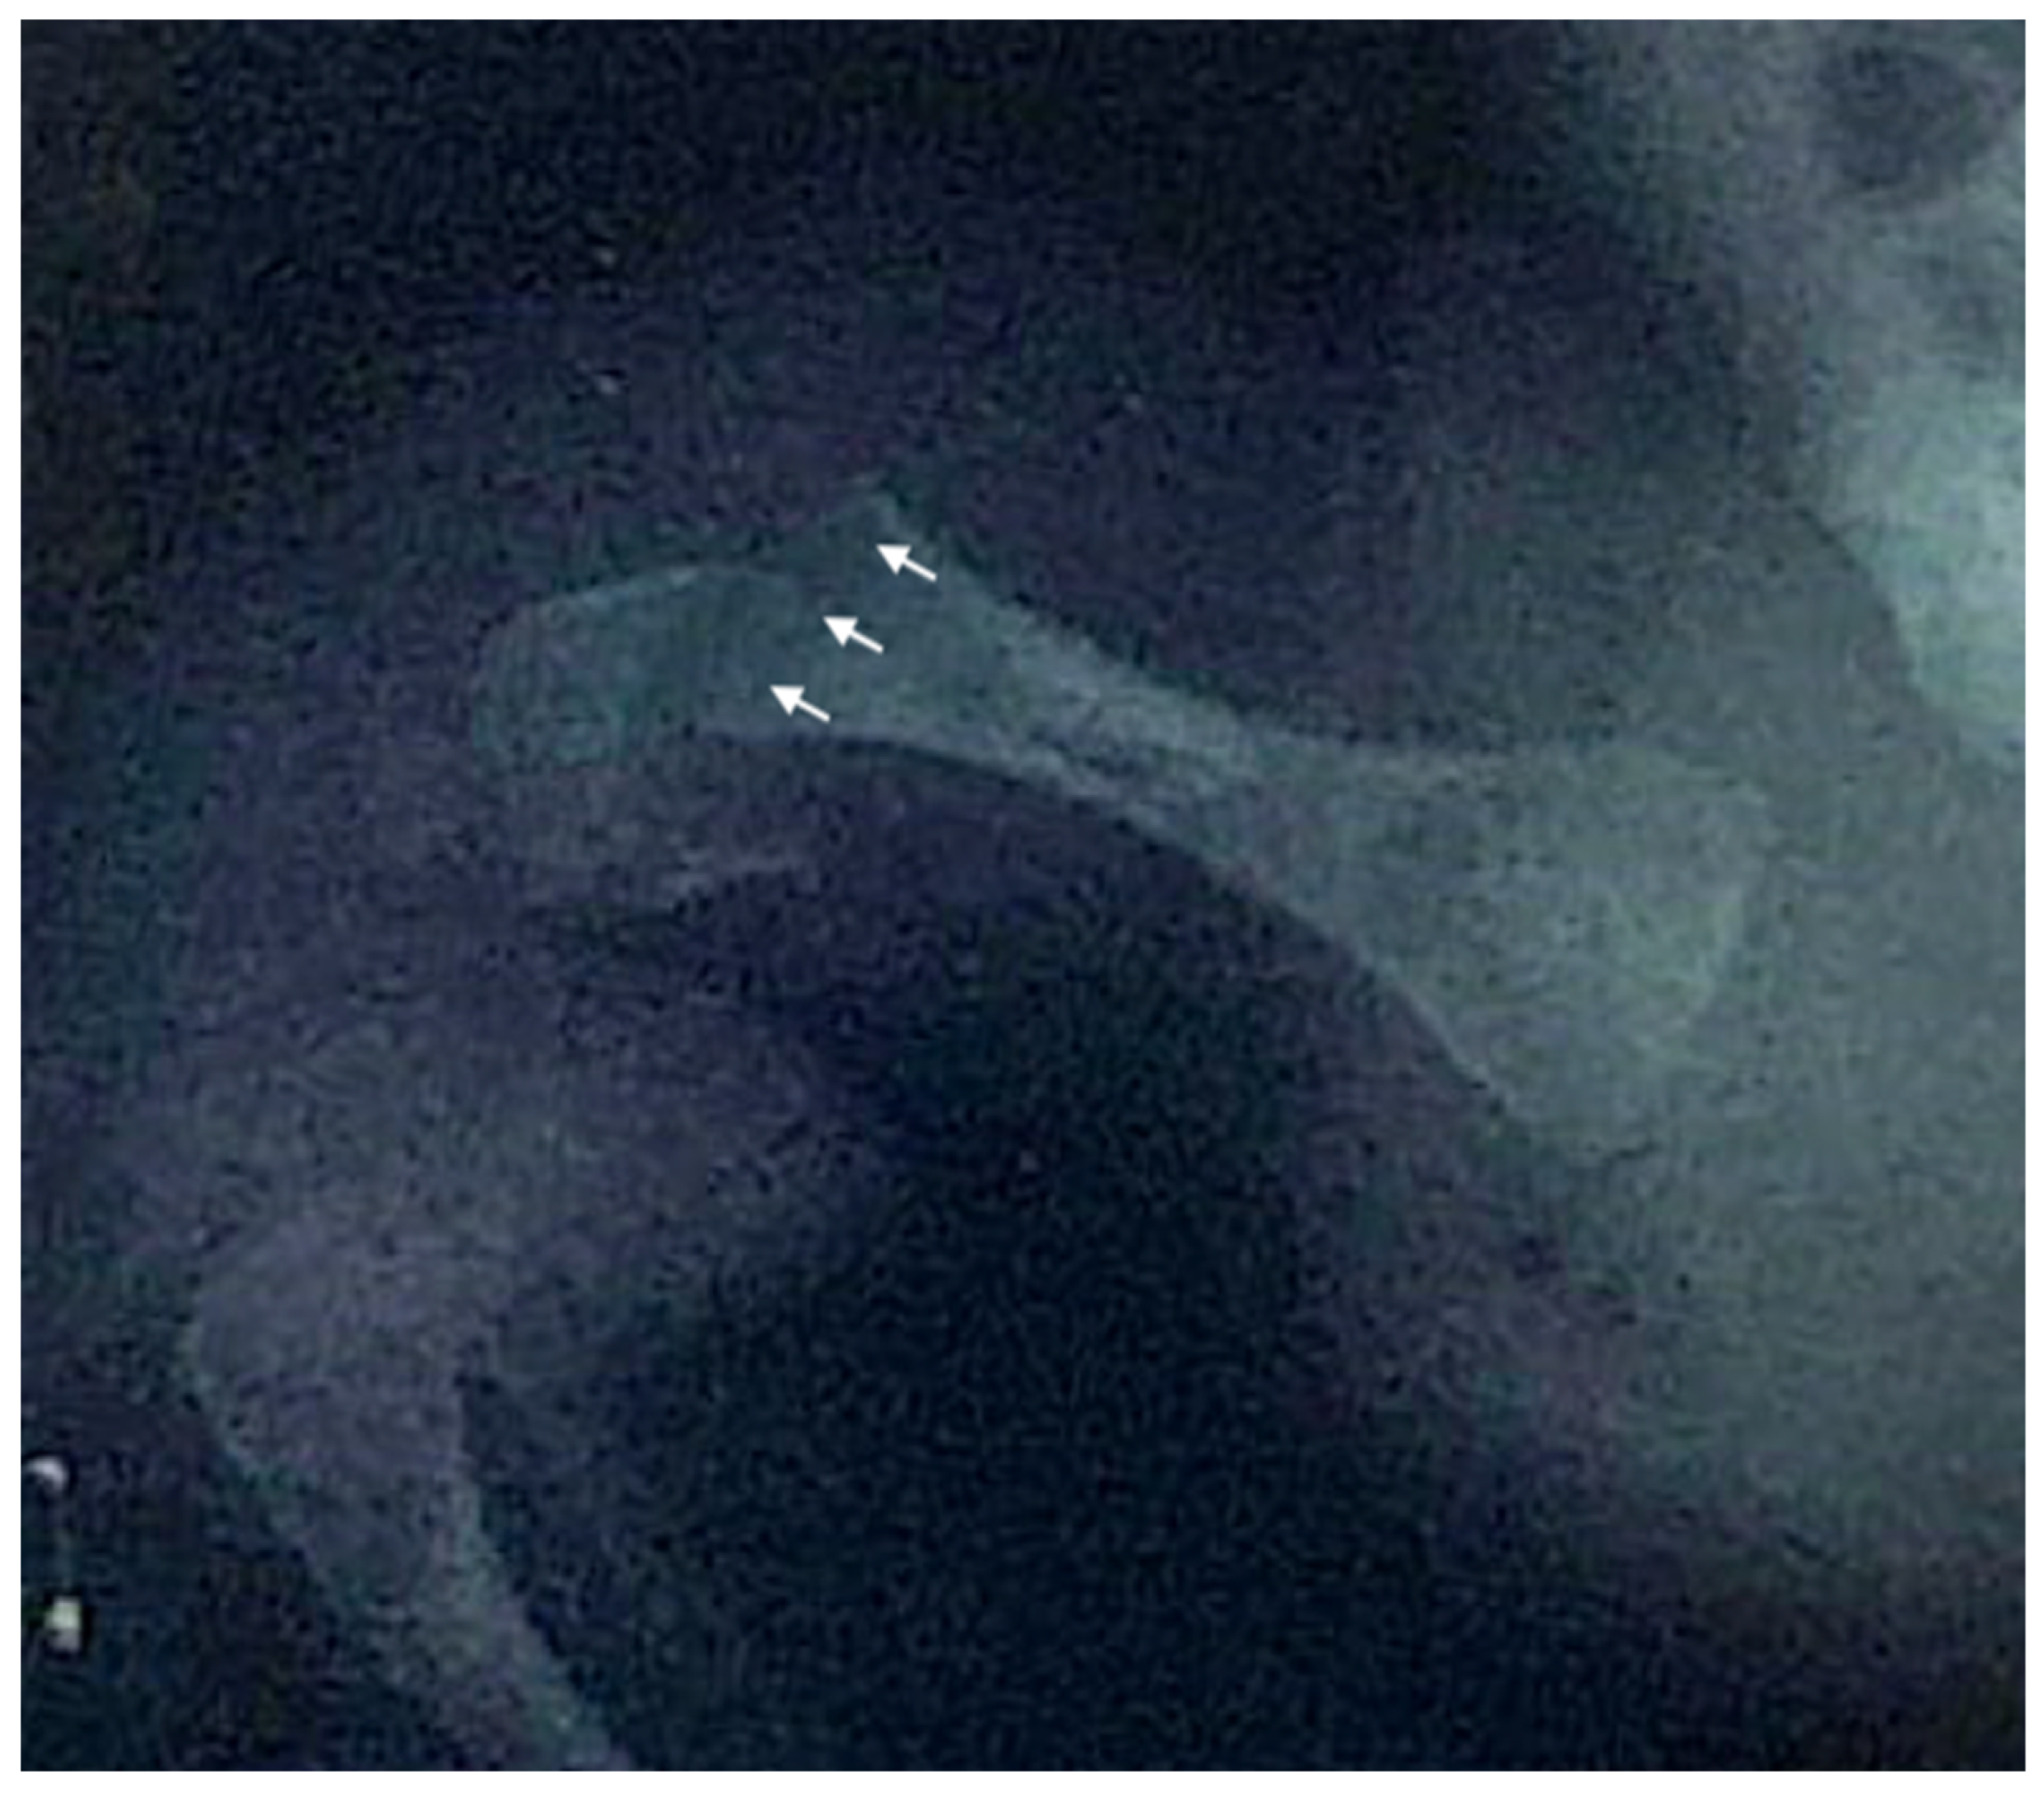

We report the case of a 21-year-old Italian male diagnosed with OI type XIV who received bisphosphonate treatment since the age of one month. The patient was referred to our hospital’s Endocrinology Department following the detection of femoral and humeral fractures present at birth, with no known family history of skeletal disorders. He was delivered at 39 weeks of gestation via elective cesarean section due to podalic presentation. Apgar scores were eight and nine at 1 and 5 minutes, respectively. At birth, his weight was 2950 g (15° p), length 46 cm (3° p), and head circumference 35 cm (66° p). On the second day of life, the swelling of the right humerus and right femur prompted radiographic evaluation, which confirmed fractures in both bones (Figure 2). Initial investigations, including echocardiography and transfontanellar ultrasound, revealed no significant abnormalities. Laboratory tests, encompassing complete blood count, biochemical profile, and bone metabolism markers, were within normal limits.

Figure 2. Anteroposterior X-ray of the right hip and proximal femur of the newborn, demonstrating a right femoral fracture. Arrows indicate the fracture line through the distal femoral shaft and associated cortical discontinuity.